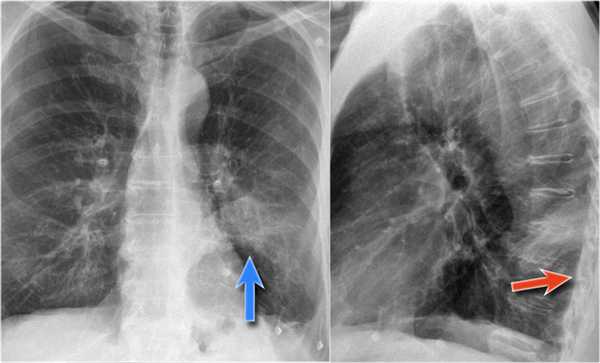

Но случаются ситуации, когда мы не видим никаких изменений, как на обзорной рентгенограмме в данном случае: практически легочные ткани. Но, посмотрите - корень левого легкого располагается на одном уровне с корнем правого легкого. Это позволяет нам предположить, нет ли тут какого-то процесса, который приводит к уменьшению объема.

На боковой рентгенограмме мы видим ателектаз язычковых сегментов, который в данном случае скрыт за тенью сердца. Именно этот процесс и вызывает смещение корня легкого.

Также очень частым проявлением ателектаза является подъем диафрагмы, что хорошо визуализируется на ниже представленной рентгенограмме (указано синий стрелкой).

У данного пациента карцинома легкого с билатеральным метастазированием в легкие (указано красными стрелкам).